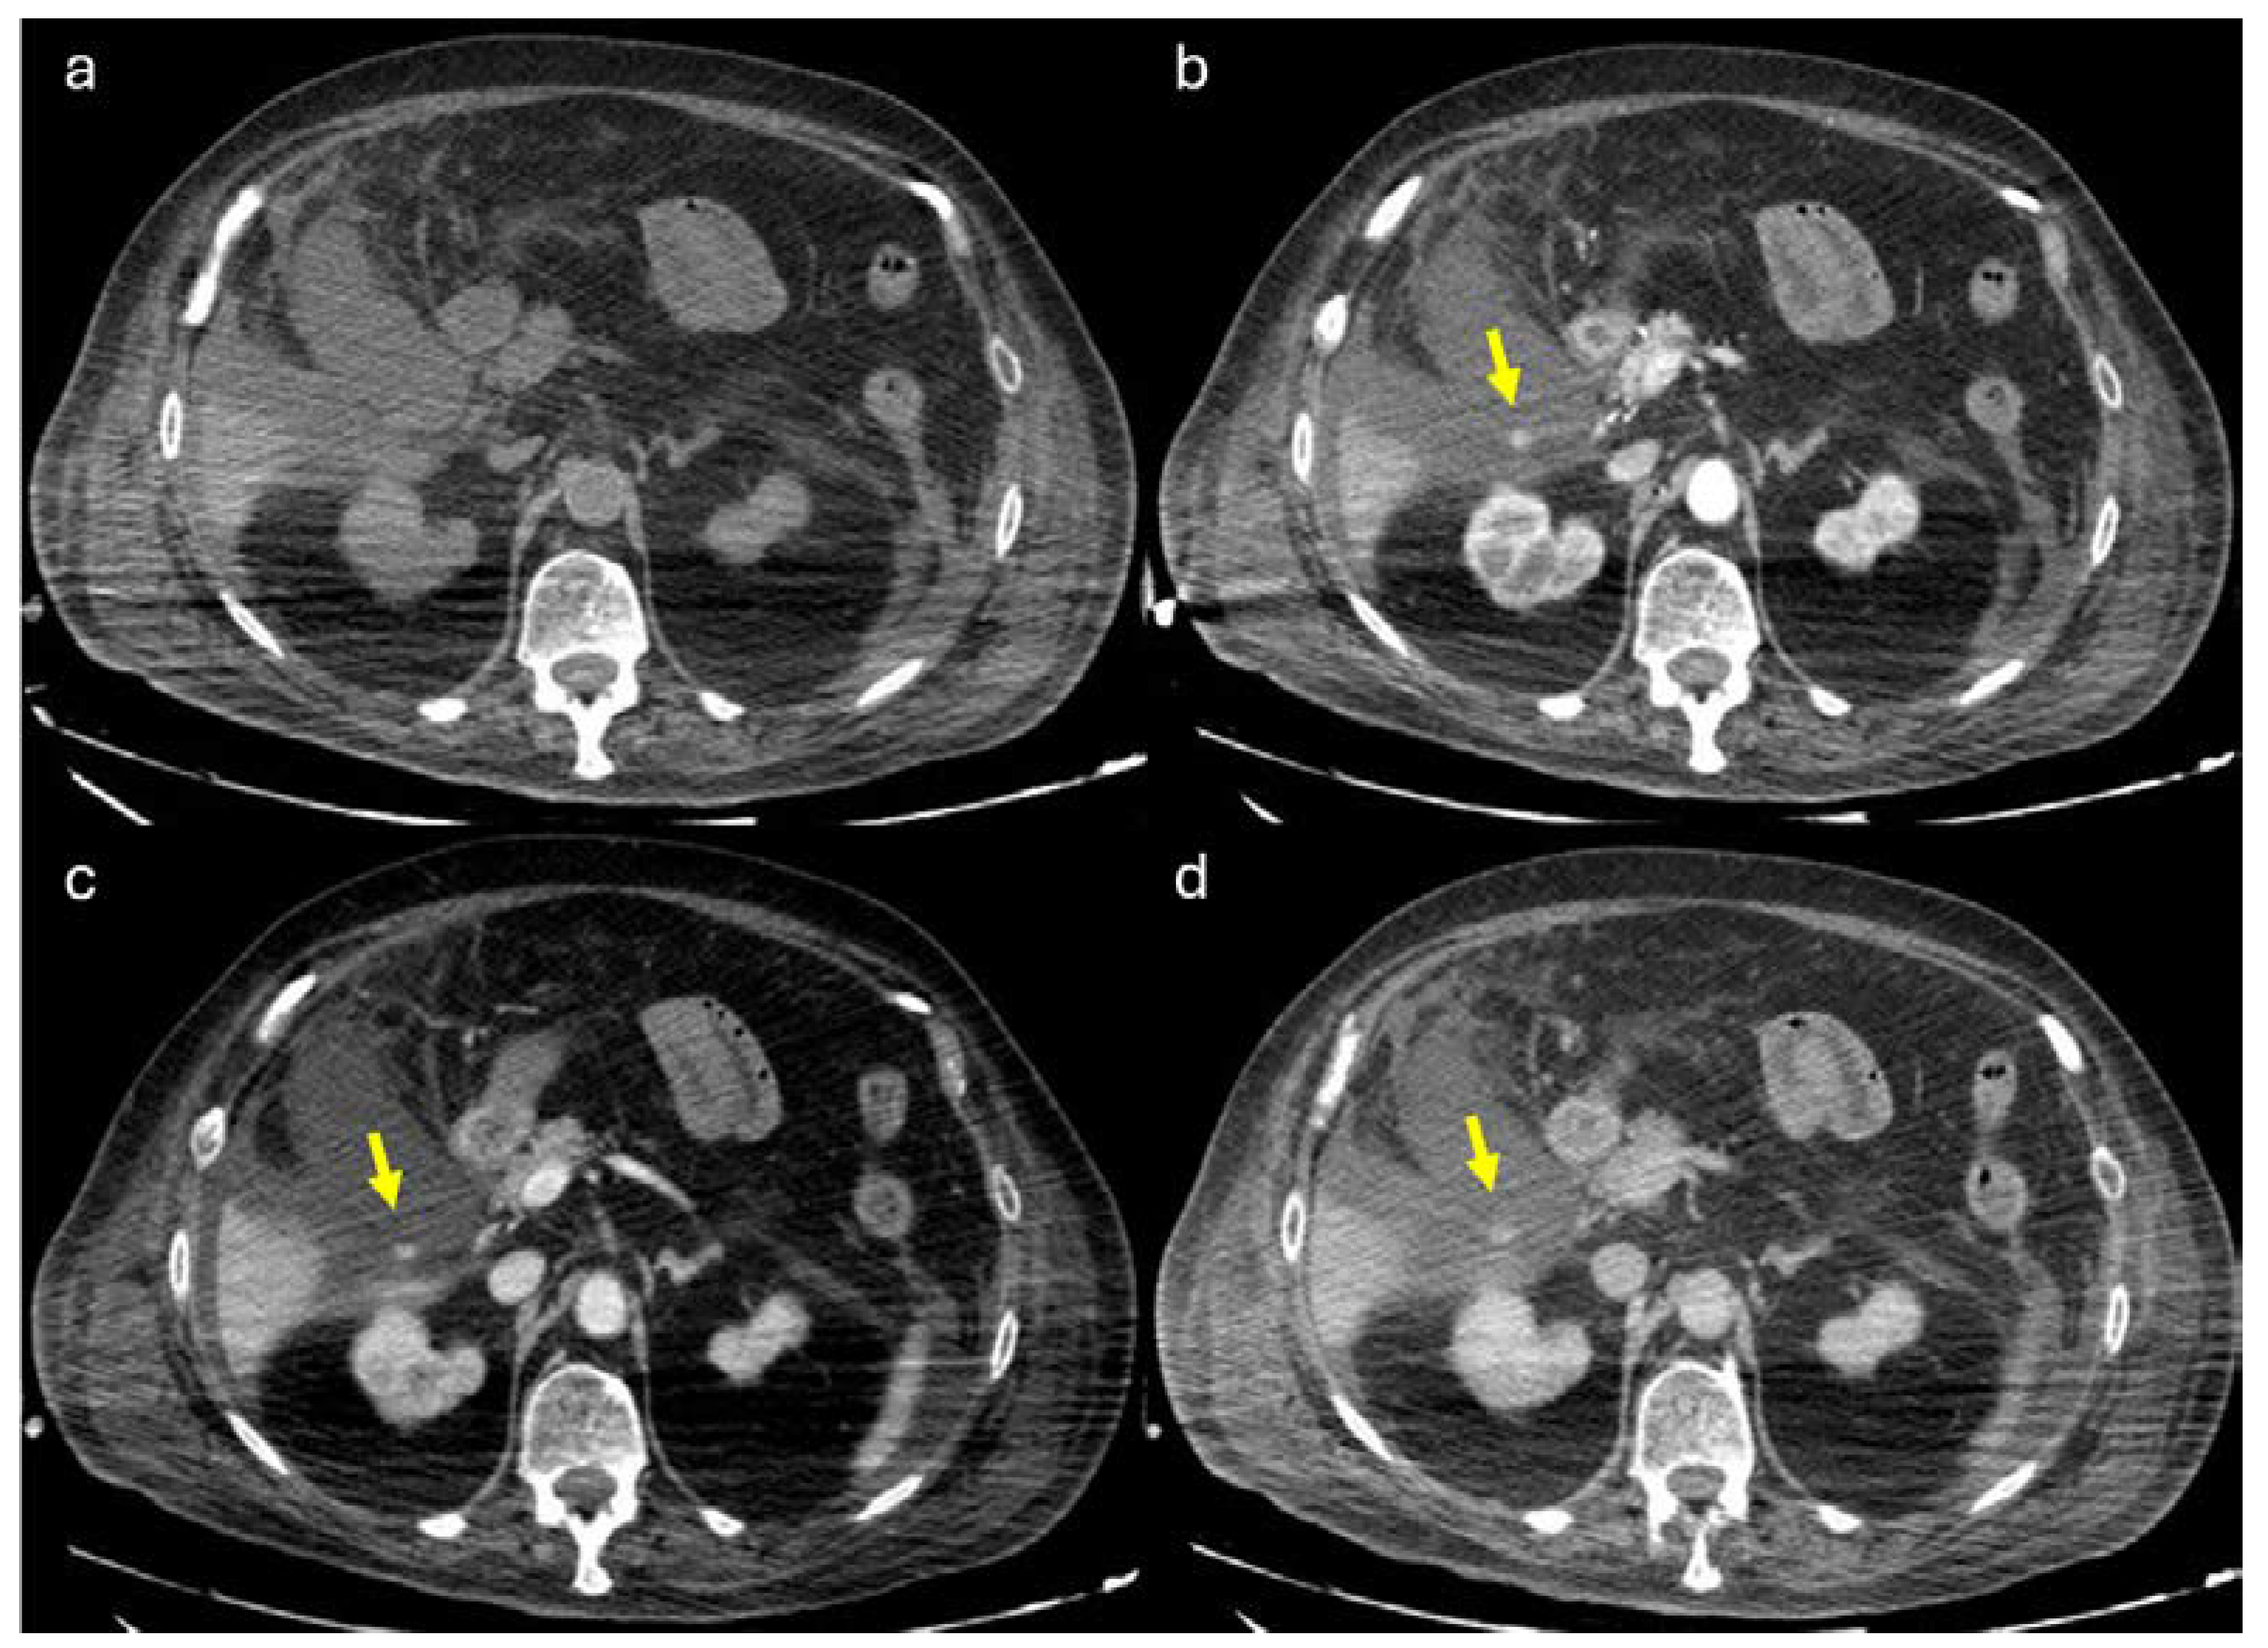

Figure 1.

74 years old male hospitalized for hip fracture who underwent arthroplasty (Hb 8 g/dl, n.v. 13-18; PRO B NP 39473 pg/ml, n.v. <375; PCR 5,04 mg/dl, n.v. 0.0-0.5; WBC 7,25 103/mm3 n.v. 4.2-10.5), who suddenly complained jaundice, right upper quadrant pain and melena. He underwent abdominal CT with IV contrast (a non-contrast, b arterial, c venous, d delayed phase), which showed a distended gallbladder with slightly hyperdense content and a rounded hyperattenuating focus (white arrow) that did not change form and was isodense to blood pool in the venous and delayed phases. Diagnosis: CAP with no active bleeding. The patient underwent cholecystectomy and was discharged on.

Following intravenous (IV) contrast administration, extravasation of contrast material may be evident within the gallbladder fossa, potentially along the course of the cystic artery’s anterior or posterior branches. A cystic artery pseudoaneurysm (CAP) can be identified as a hyperenhancing focus during the arterial phase along the cystic artery branches. This finding demonstrates a change in attenuation but not morphology in the venous and delayed phases (

Figure 1). In CAP active bleeding extravasation, is detected around the oval/round pseudo aneurysmatic sac. Because of the possible presence of pre-existing gallbladder stones or surgical clips for previous cholecystectomy, images should be examined carefully in different CT phases in order to differentiate hyperdense material appearing in an angiographic phase that should not be present at the same location in non-contrast images, delayed images can be useful in differentiating between active extravasation or CAP and relatively benign process [